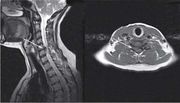

| 14:34, 14 августа 2017 | Bol spina18.jpg (файл) | 16 КБ | Магнитно-резонансная томограмма шейного отдела позвоночника. Перамедиальная правосторонняя грыжа диска С5-С6 с компрессией спинного моз… | 1 | |